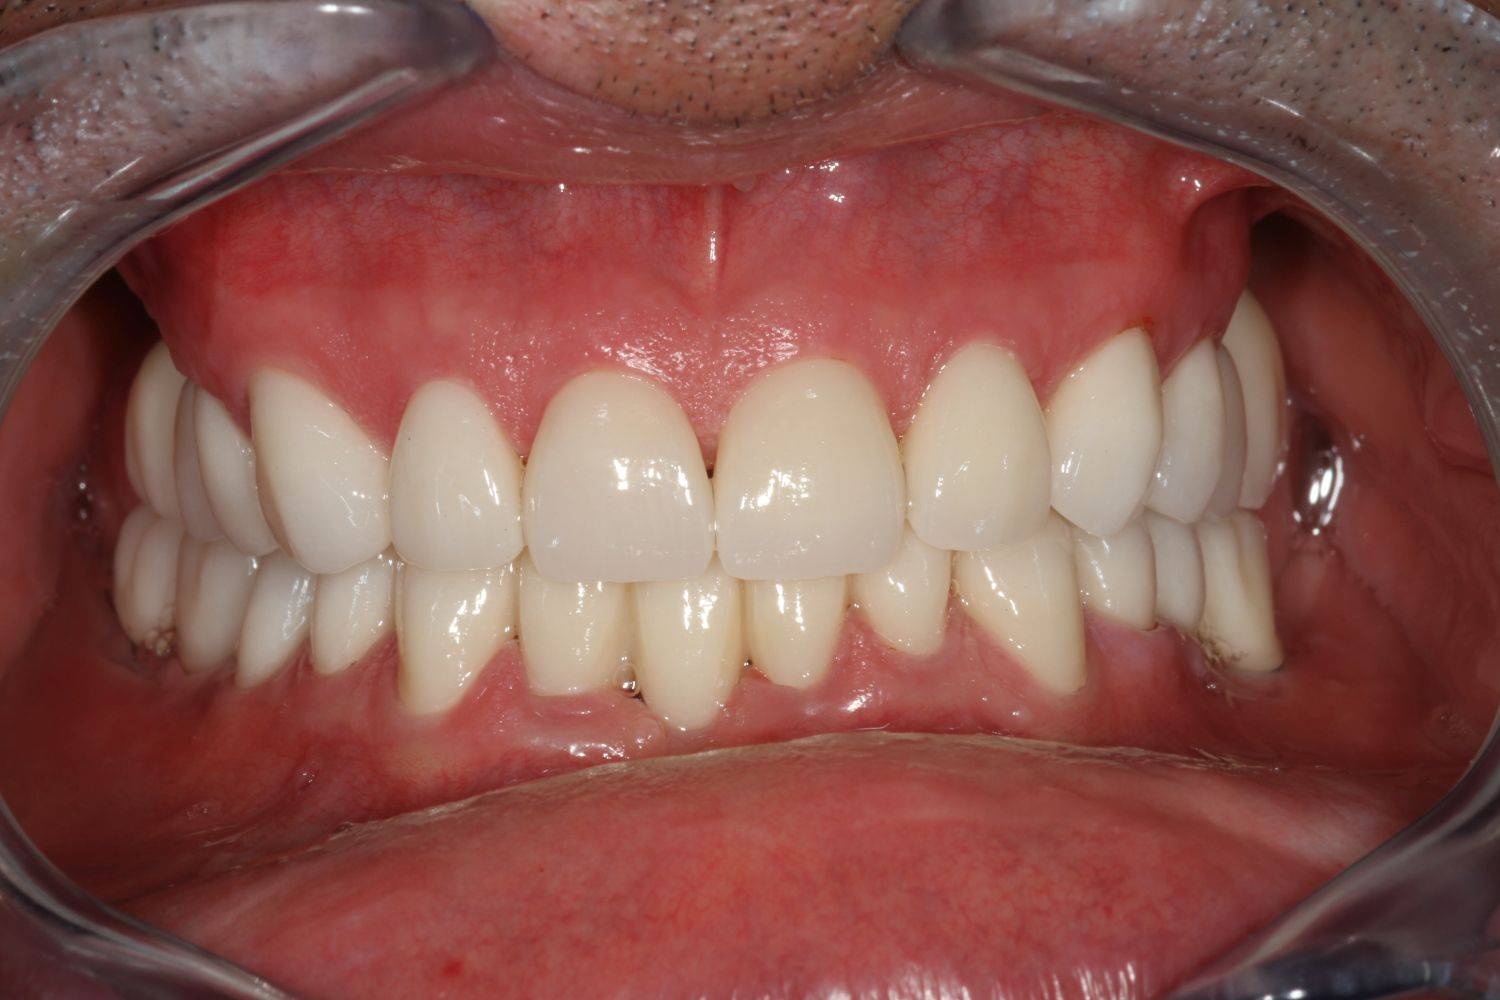

10. eset

Savas kémhatású anyagok, mint például a szénsavas üdítők túlzott használata is a fogak zománcrétegének nagyfokú károsodását okozhatják. 35 éves férfi páciensnek készítettünk a frontfogaira Zirkon koronákat, a rágófogaira pedig fémkerámia szóló koronákat. 28 koronával állítottuk helyre a fogazatot.